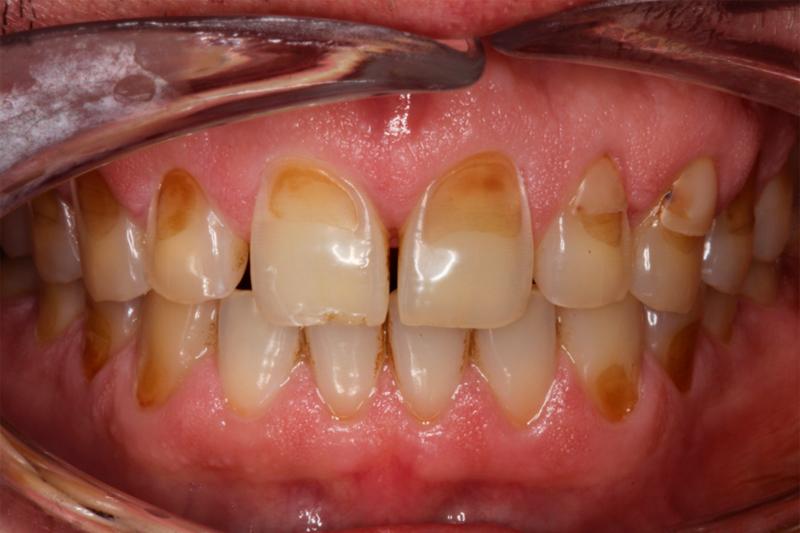

Эрозия зубов — это прогрессирующее необратимое истирание зубной эмали или дентина в результате химического растворения кислотами. Помимо эстетического дефекта и проблем со здоровьем полости рта, эрозия может привести к повышенной чувствительности и возможной потере пораженных зубов.

• Изменение цвета зубов. Зубы могут казаться более желтыми из-за обнажения дентина

• Прозрачность. Края передних зубов могут стать прозрачными.

• Трещины и вмятины. Если зубная эмаль начинает разрушаться, на зубах могут появиться трещины и небольшие вмятины вдоль жевательной поверхности. Когда эмаль разрушается, значительно увеличивается риск развития кариеса.